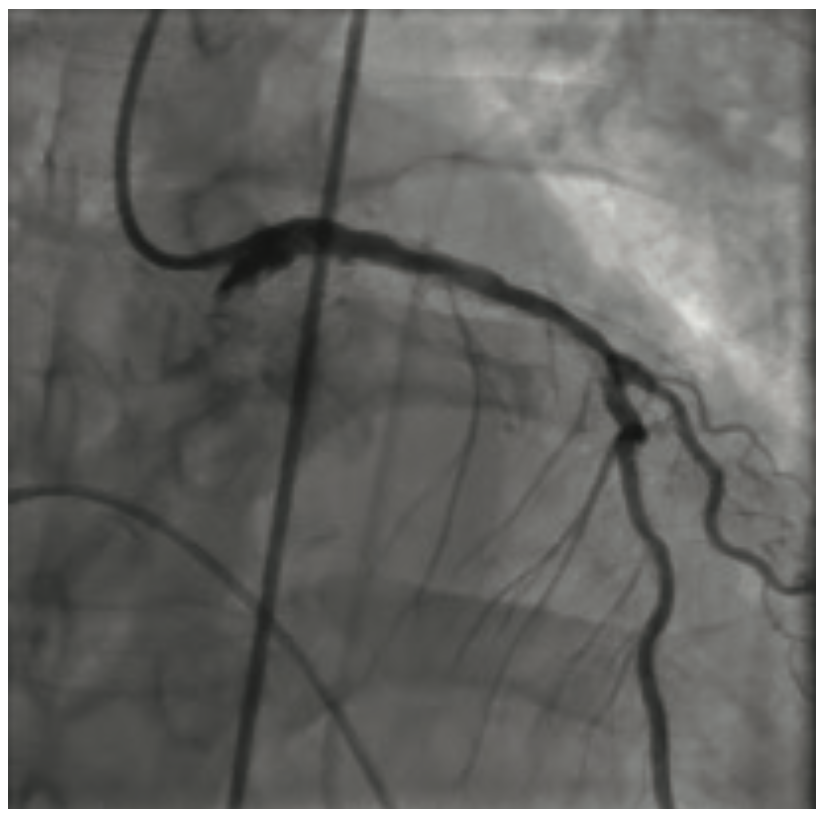

He clinically improved and on the second hospital day, underwent diagnostic cardiac catheterization. He did not have palpable radial pulses bilaterally; therefore, a femoral approach was used. His right external iliac artery and right common femoral artery were occluded. His distal aorta was heavily calcified with a high-grade eccentric stenosis. He also had a proximal 70%-80% left common iliac artery stenosis. Diagnostic coronary angiographic findings demonstrated a heavily calcified ostial 99% lesion in the right coronary artery (RCA) with significant calcium accumulation throughout the mid RCA. The left main coronary artery appeared heavily calcified, with a wedge-shaped filling defect suggesting a high-grade eccentric stenosis. The proximal left anterior descending (LAD) artery was very tortuous with a heavily calcified lesion at the first diagonal that extended into the ostium of the diagonal vessel. The circumflex artery was totally occluded. The patient’s ejection fraction based on ventriculography was 35% to 40%, with the posterior lateral wall being akinetic. He was extubated following the cardiac catheterization. Cardiothoracic surgery was consulted to provide an opinion regarding surgical revascularization. Due to his multiple comorbidities, he was felt to be high risk and not a surgical candidate. A plan for percutaneous revascularization was discussed with the patient. The nature and purpose of the procedure along with expected outcomes, together with the reasonably known risks were explained. He acknowledged that such disclosure of information had been made and that all questions asked about the procedure had been answered. He demonstrated understanding and legal capacity to consent and therefore, the written consent was obtained by his signature. The intervention was performed on hospital day 5. The patient was discharged home on hospital day 7.

The RCA was initially treated with orbital atherectomy. The 1.25 mm x 145 cm Diamondback 360˚ orbital atherectomy system (CSI) was advanced over the wire. Multiple passes at low speed were performed to reduce the ostial RCA lesion. Treatment was performed from proximal to distal, with the tip of the catheter crown just within the ostium prior to spinning. After multiple passes, luminal gain was observed angiographically in the ostial portion of the vessel. The crown was then traversed on low speed through the mid RCA just proximal to the distal portion of the vessel. Balloon angioplasty was performed prior to deploying two drug-eluting stents to cover the orbital atherectomy treatment zone from the distal RCA retrograde to cover the RCA ostium. No slow flow or dissections were noted angiographically and the patient remained hemodynamically stable throughout the RCA intervention. A Xience Skypoint 2.75 mm x 33 mm stent (Abbott Vascular) was advanced into the distal RCA and deployed at 12 atmospheres (atm). This was followed by a 3.0 mm x 33 mm Xience Skypoint stent, deployed in the mid RCA, and finally, a 3.5 mm x 28 mm Xience Skypoint stent was deployed proximally. The stents were post dilated with a 3.0 mm x 20 mm, 3.5 mm x 20 mm, and 4.0 mm x 20 mm NC Trex RX balloon (Abbott Vascular) at 20 atm. Completion angiography was performed. We chose to proceed to treating the left coronary tree.

The left main artery was cannulated with a 6 Fr XBLAD 3.5 guiding catheter (Cordis). The Whisper wire was used to cross the stenosis. IVUS was performed using an .014 Eagle Eye Platinum ultrasound catheter (Philips Volcano). In the same fashion as the RCA, the Whisper wire was exchanged for the ViperWire. The LM was subsequently treated with orbital atherectomy. Multiple passes were performed in opposition to the 70% nodular, calcified lesion that was fully identified on IVUS imaging. Once luminal gain was identified angiographically in the LM, the atherectomy crown was traversed distally into the calcified lesion in the proximal LAD. After two passes in the proximal LAD, the crown was traversed into the mid LAD lesion at the level of the first diagonal branch. Orbital atherectomy was again performed, reducing the calcium burden in both the LAD and the ostium of the diagonal branch. Balloon angioplasty was performed from mid LAD retrograde to the LM using a 3.0 mm x 20 mm NC Trek balloon. Following the balloon angioplasty, drug-eluting stents (3.0 mm x 15 mm Xience Skypoint, 3.5 mm x 38 mm Xience Skypoint, and a 5.0 mm x 30 mm Resolute Onyx drug-eluting stent [Medtronic], placed distal to proximal) were deployed from the mid LAD proximally to the LM, covering the orbital atherectomy-treated zone. The patient remained hemodynamically stable throughout the procedure. A completion angiogram was obtained. No slow flow or dissections were noted.